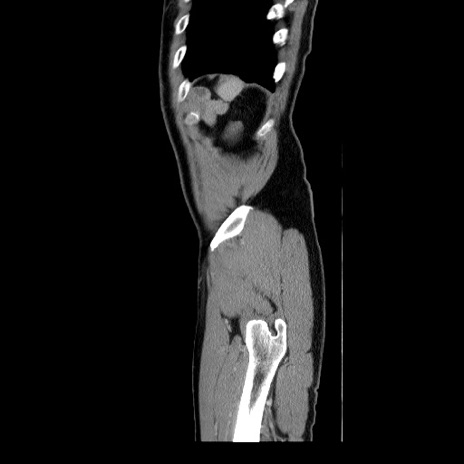

症例34(矢状断像)

【症例】60歳代 男性

【主訴】右鼠径部膨隆

【現病歴】1年程前より右鼠径部膨隆あり。自己にて還納可能だったため放置していた。3時間前より右鼠径部の脱出を認め、還納困難となり受診。

【身体所見】右鼠径部に小児頭大の膨隆あり。弾性硬であり、用手還納は困難。左鼠径部にも膨隆を認める。脱出はなし。